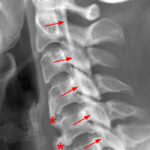

[doctormodu]1 OPLL x ray

10 후방종인대골화증OPLL, 황색인대 골화증 OYL